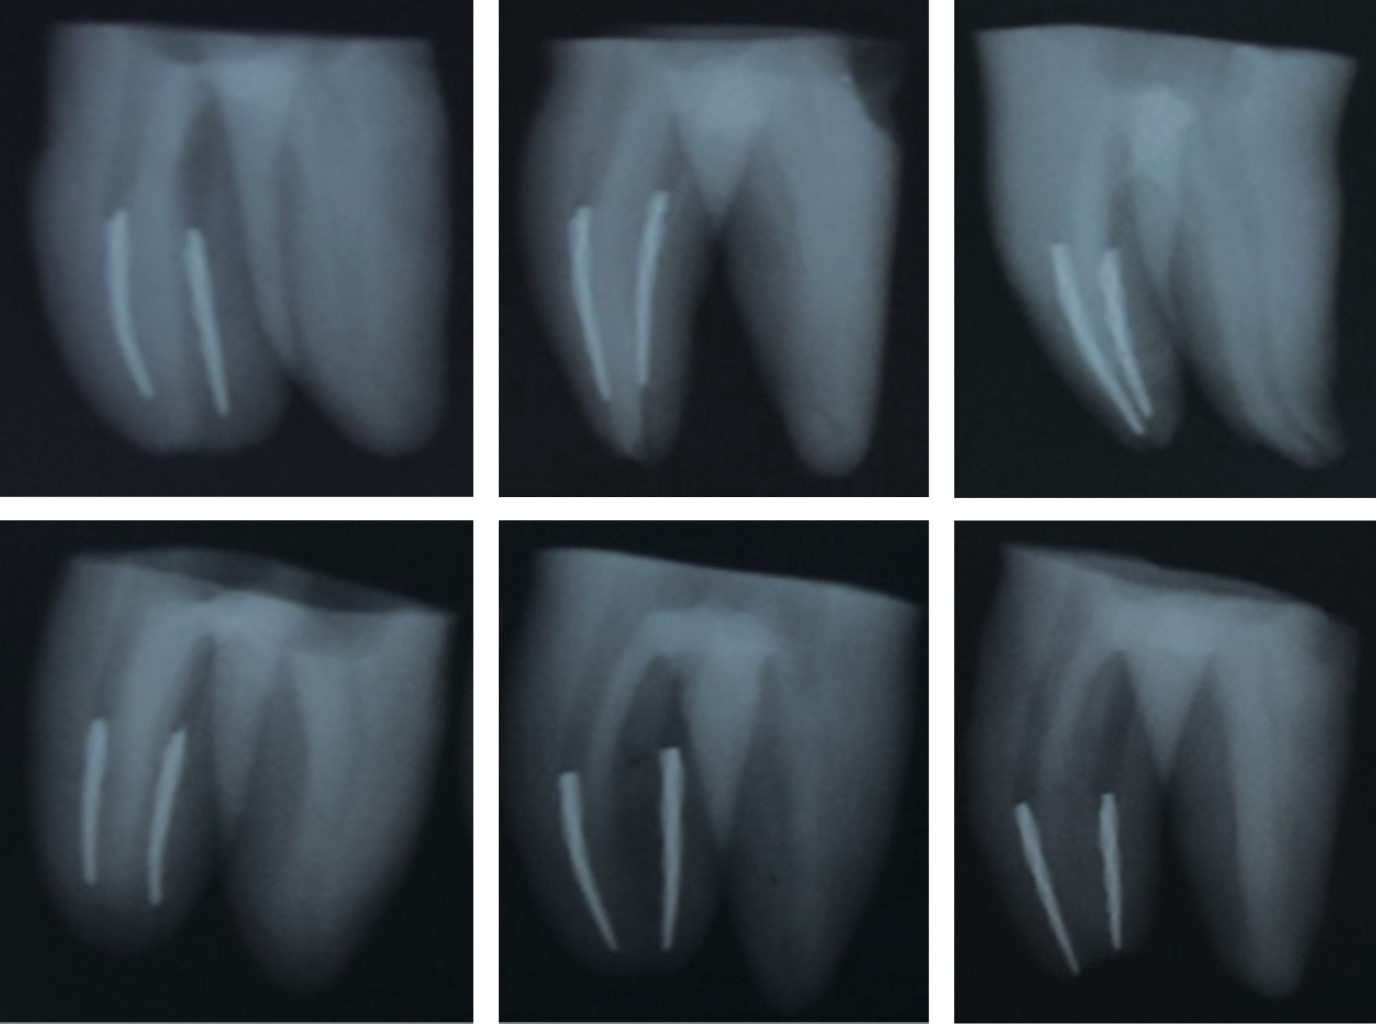

Terminada la fase de instrumentación se procedió a la fractura intencional de las limas. Se les hizo un desgaste mínimo en todas sus caras, los primeros 4 milímetros de la parte activa con la ayuda de una fresa troncocónica de carburo #2 (Figura 1), se llevaron al conducto radicular hasta alcanzar la longitud de trabajo previamente establecida y se activó el motor endodóncico para provocar la fractura de la lima a nivel apical de todas las muestras (Figura 2). Se tomaron radiografías oclusales (Carestream dental) para comprobar que la fractura de las limas se había producido correctamente en el tercio apical (Figura 3).

Los resultados obtenidos en el presente estudio con respecto a la microfiltración apical mostraron que el grupo en el cual se utilizó la técnica de obturación condensación lateral clásica presentó una filtración media de 3.2 ± 1.7 y el grupo de la técnica de obturación termoplastificada Obtura II mostró un valor medio de 5.0 ± 2.5 (Tabla 1 y Figura 4). Por lo tanto, al llevar a cabo una comparación de medias entre ambos grupos mediante la prueba t de Student para muestras independientes se encontró con suficiente evidencia estadística una mayor microfiltración apical en el grupo de Obtura II comparado con el grupo de condensación lateral clásica (p < 0.002).